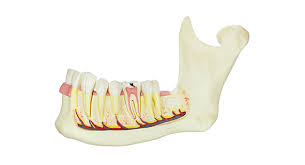

하치조 신경이란?

하치조신경

하악의 어금니 치아 아래로

하치조 신경관이 지나고 있습니다.

아래턱 신경부터 턱뼈관으로 들어가 아래 치아와

아래턱뼈에 분포하고 있는 신경입니다.

삼차 신경의 세 분지 중 하나로 치아와 잇몸은

물론 턱, 입술의 감각에 큰 영향을 미치므로

손상을 입지 않도록 유의해야 합니다.